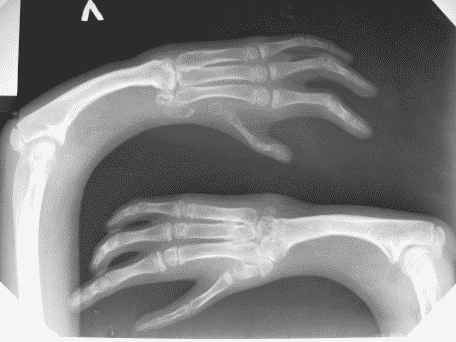

Мальчику 12 лет, страдает аномалией развития верхних конечностей. Ребенок был оперирован несколько раз в другом городе. На сегодняшний день у пациента выражена деформация левого предплечья и оба предплечья короткие. У пациента и родителей есть желание удлинить предплечья.

Функция кистей нарушена, сгибание в локтевых суставах в полном объеме.

Скажите, пожалуйста, что Вы думаете по поводу удлинения предплечий. На сколько сантиметров  можно  удлинить, и будет ли польза больному от этого .